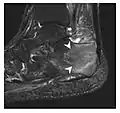

Triquetral fracture usually occurs on the dorsal aspect by impingement from the ulnar styloid or avulsion of strong ligamentous attachment. The dorsal avulsion fracture or "chip fracture" appears as a small bony fragment on the dorsal aspect of the triquetrum and is best detected on the lateral view(Figure 4). When radiography is negative in patients with high suspicion of a fracture, both MRI and MDCT will be of value. However, it has been shown that MRI is superior for detecting trabecular fractures in carpal bones.

Figure 4: Dorsal triquetral fracture of the left wrist in a 30-year-old man after a trauma. (a) Anteroposterior radiograph shows a normal appearance. (b) Lateral radiograph of the same wrist demonstrates a chip fracture off the dorsal aspect of the triquetrum (arrow).[1]